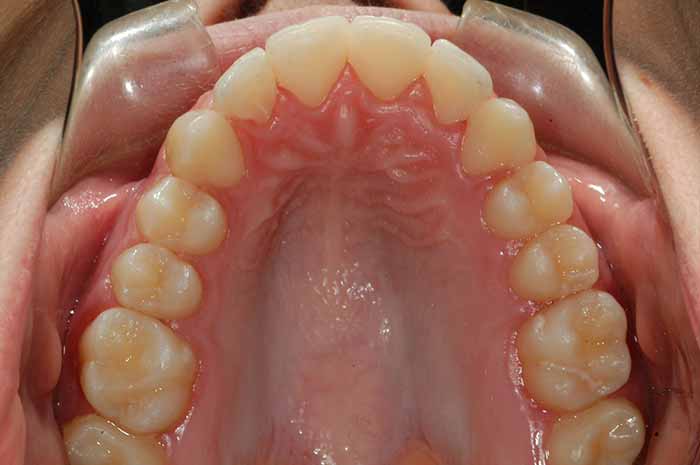

Problema:

Mordida cruzada anterior

Uno o varios incisivos superiores se situan por detrás de los inferiores, pudiendo alterar el correcto cierre de la boca.

Antes y Después